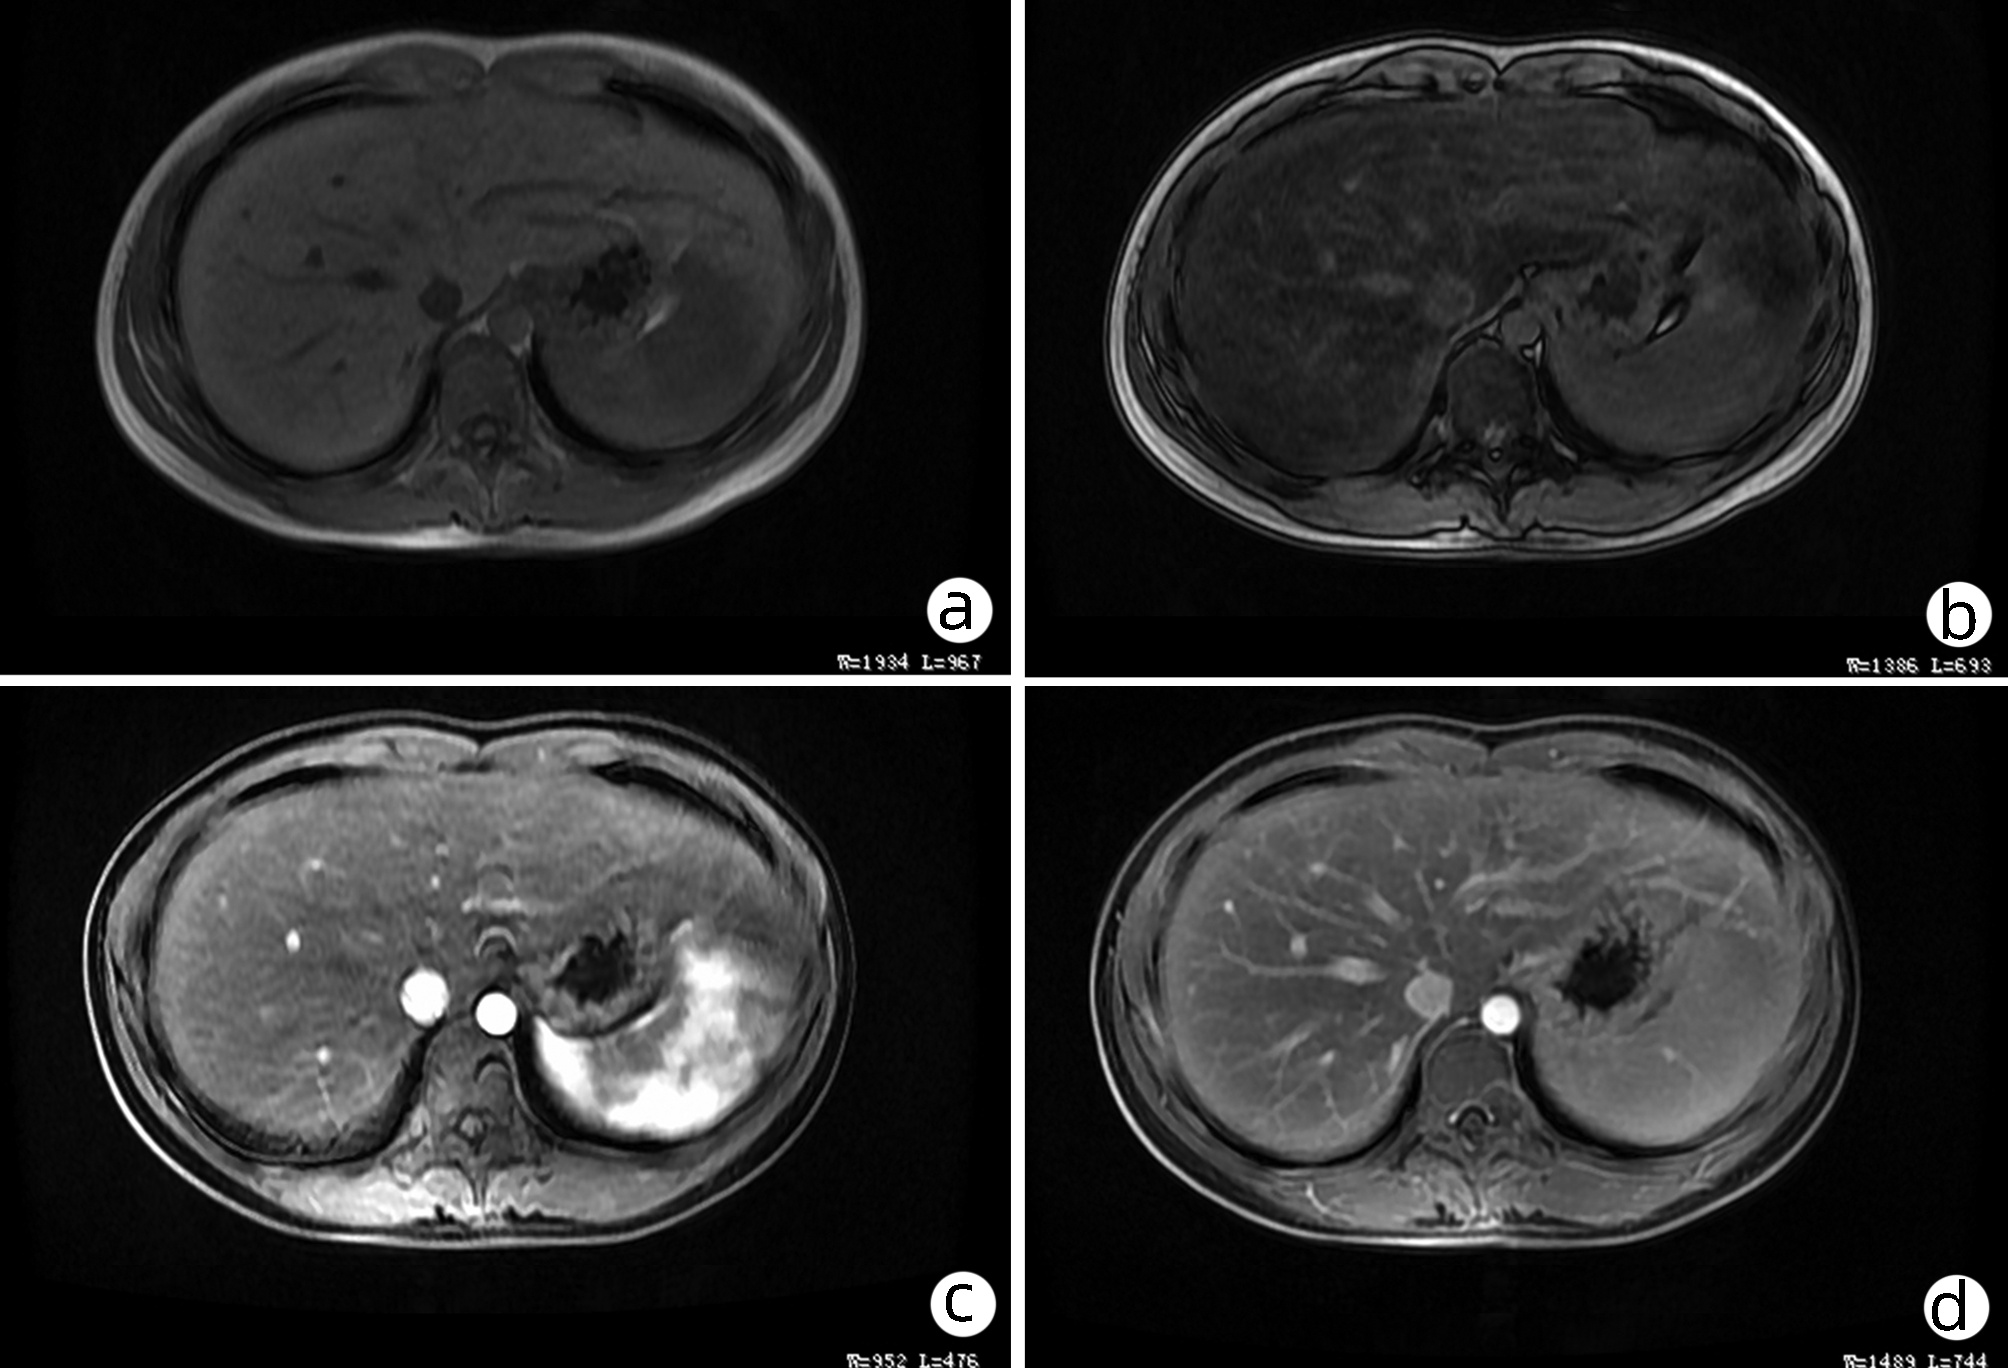

Late-onset diaphragmatic hernia after microwave ablation of hepatocellular carcinoma: A case report

Xiaodong WANG, Yurong ZHANG, Xiaoning ZHU, Ding ZHENG, Jing WANG

2022, 38(8): 1875-1877. DOI: 10.3969/j.issn.1001-5256.2022.08.029

Abstract(895) HTML (335) PDF (2572KB)(68)

Abstract: